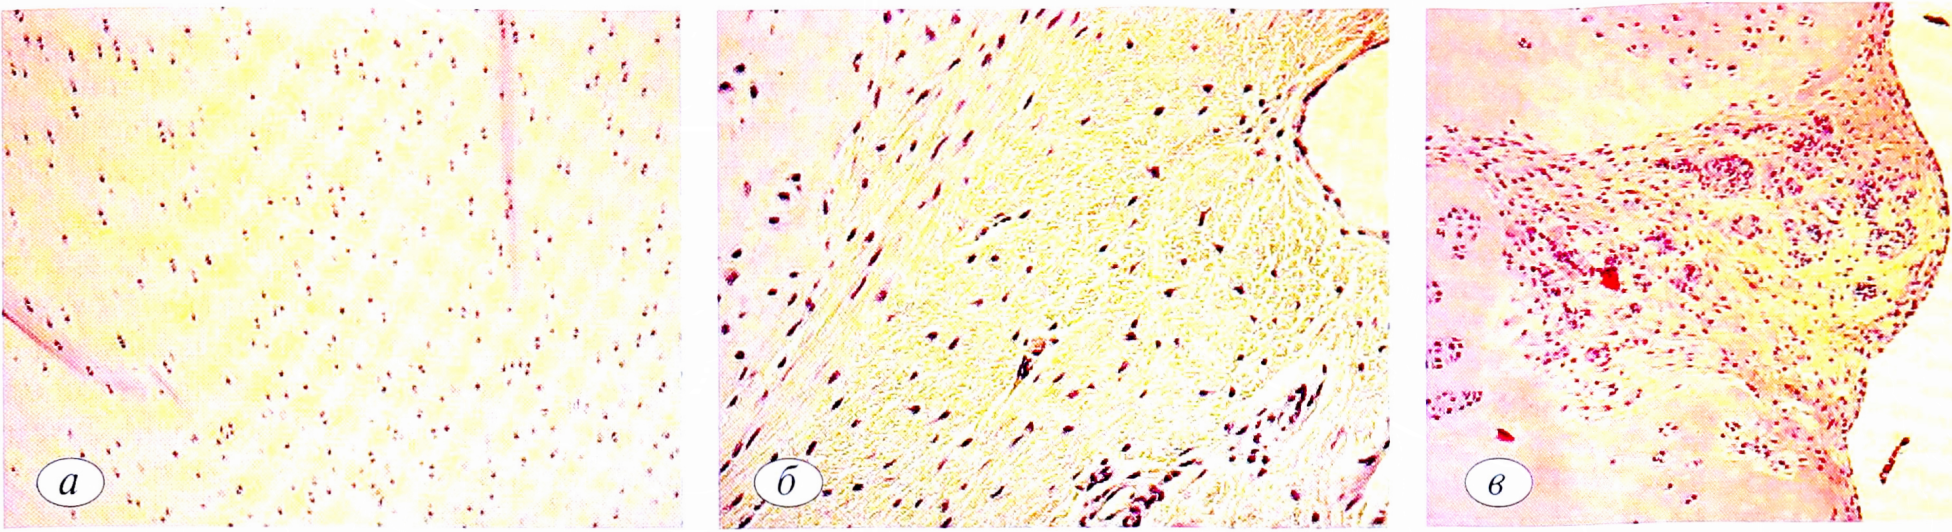

Рис. 6. Микроскопическая картина после закрытия дефекта ВКМ в динамике, где: а — 1 мес; б — 3 мес; в — 6 мес. Увеличение ×40.

Fig. 6. The Microscopic picture after closure of the defect VCR in dynamics, where: a — 1 month; b — 3 months; c — in 6 months. Magnification ×40.

Результаты, полученные в 1-й группе, отражают неполноценность сформированного сгустка и его ранний лизис после микрофрактурирования. Во 2-й группе эксперимента показатели регенерации имели положительные отличия от таковых в 1-й группе, что связано с применением ВКМ. Наиболее оптимистичные результаты наблюдали в 3-й группе, в которой остеохондральный дефект максимально заполнен регенератом гиалиновоподобной хрящевой ткани с морфологически прослеженной архитектоникой (рис. 7,8). По мнению нашей исследовательской группы, это может свидетельствовать о хороших результатах сочетания микрофрактурирования и коллагенового матрикса со взвесью аутохондроцитов в плазме, обогащенной тромбоцитами, что позволяет рекомендовать методику к клиническому применению.

Рис. 7. Динамика макроскопической картины в третьей экспериментальной группе. Внешний вид дефекта: а — через 1 мес; б— через 3 мес; в — через 6 мес.

Fig. 7. Dynamics of the macroscopic picture in the third experimental group. Appearance of the defect: a — after 1 month; b — after 3 months; c — in after 6 months.

Рис. 8. Микроскопическая картина дефекта в динамике, где: а — 1 мес; б — 3 мес; в — 6 мес. Увеличение ×40.

Fig. 8. Microscopic picture of the defect in dynamics, where: a —1 month; b —3 months; c — in 6 months. Magnification ×40.

Наиболее выраженную картину восстановления дефекта отметили к 6 мес после операции в 3-й экспериментальной группе. Дефект при макроскопическом исследовании практически полностью восстановлен с ровными гладкими краями и плавным переходом границы между новообразованной тканью и сохраненным гиалиновым суставным хрящом. Разделительная линия между ними прослеживается с трудом (рис. 5, а).

На гистологических срезах в этой группе отчетливо видно, что на месте бывшего повреждения образовался неоднородный слой гиалиноподобного хряща, сопоставимый по морфологическим и качественным показателям с нативным.

Микроскопически область костно-хрящевого дефекта по краям выполнена гиалиновоподобной хрящевой тканью, которая местами разделялась на слои (поверхностный, промежуточный, глубокий). Субхондральная костная пластинка восстановлена на всем протяжении; волокна ее утолщены, оформлены. В большинстве своем элементы костной ткани ориентированы пространственно перпендикулярно кортикальной пластинки, основное вещество в умеренном количестве, гомогенное (рис. 5, б).

Рис. 5. Динамика макроскопической (я) и микроскопической (б; ув. 40) картины в 3-й экспериментальной группе. а — через 1 мес; б — через 3 мес; в — через 6 мес.

Fig. 5. Dynamics of macroscopic (a) and microscopic (b); magnification 40) pattern in the 3rd experimental group. a — after 1 month; b —after 3 months; c —after 6 months.

Удельный объем хондроцитов в среднем составил 8,8±0,3%, хрящевого матрикса 58,6±0,8%, объем соединительной ткани 32,7±1 % соответственно. Восстановление средней глубины дефекта достигло 1,9±1,3% от нормальной толщины гиалинового хряща.